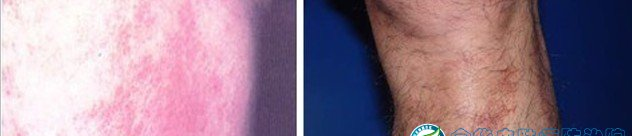

皮炎是一種常見(jiàn)皮膚病,表現(xiàn)為紅斑,表面有針尖至米粒大小的丘疹、水皰、滲透液、結(jié)痂及脫屑,也可呈現(xiàn)苔蘚樣變,自覺(jué)瘙癢,日曬和遇熱后會(huì)使癥狀加重等現(xiàn)象。醫(yī)生建議,對(duì)于已經(jīng)出現(xiàn)皮炎或者過(guò)敏癥的人,應(yīng)到正規(guī)醫(yī)院診治。下面是皮炎的圖譜,如果你懷疑自己得了皮炎,可以對(duì)照下面譜圖;

二、日光性皮炎